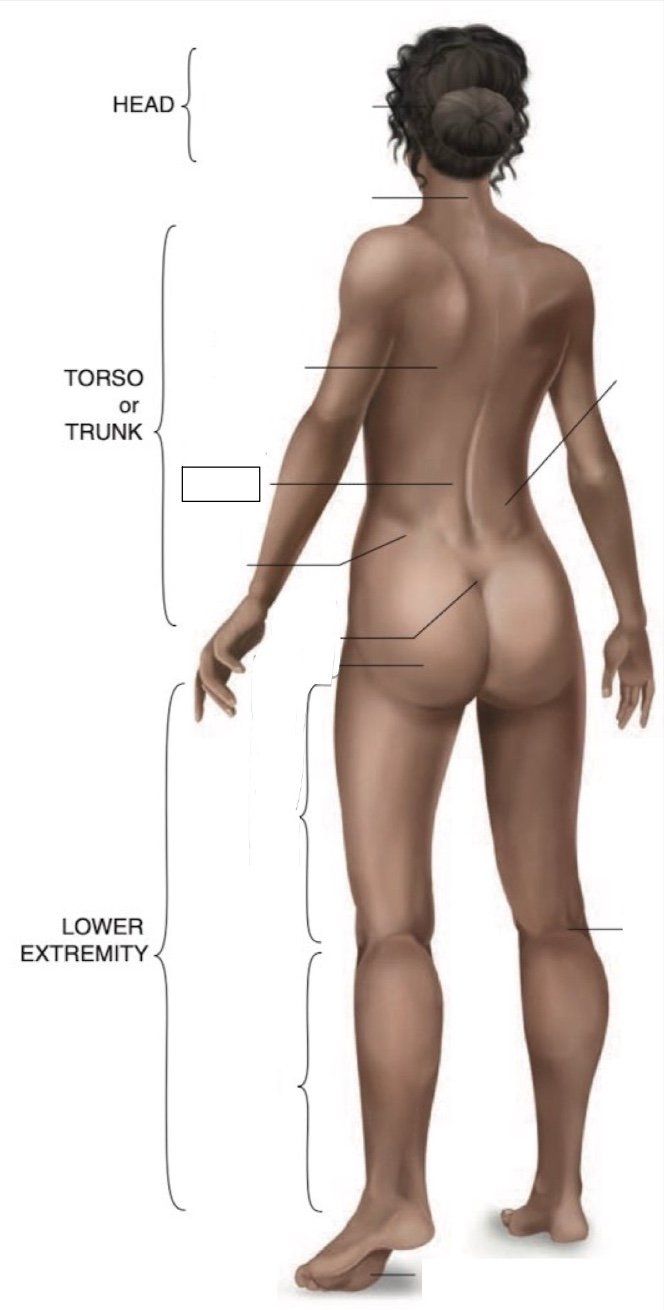

Occipital region

Cervical region

Inferior angle of scapula

Lumbar region

Iliac crest

Sacral region

Buttock

Flank